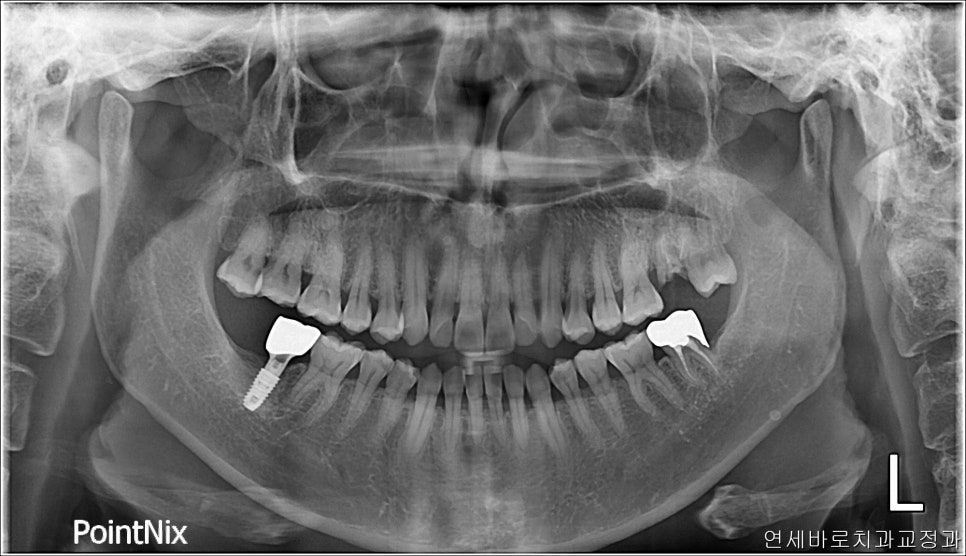

이쪽 부분에 임플란트를 심고 싶어서 오셨던 분입니다.

긴 상담 끝에 임플란트를 안하고, 뒤에 있는 사랑니를 1)돌리고 2)올리고 3)당겨오기로 했습니다

미니스크류를 사진에는 하나만 보이지만 두개 심었고,

3차원적인 이동을 하다보니 오래 걸렸어요

21.5 ~ 24.4 이니까 3년이네요 ㅠ

사랑니이기 때문에 형태도 약간은 이상했지만 아래쪽과 교합도 문제없게 만들어드렸습니다.